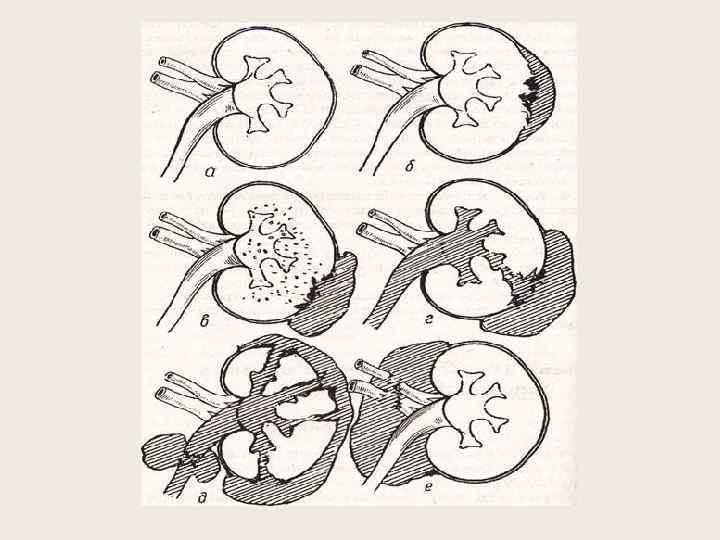

Закрытые травмы Ушиб – резкое сотрясение без разрыва паренхимы капсулы и полостной системы Разрыв 1. Наружный разрыв паренхимы, субкапсулярная гематома 2. Наружный разрыв паренхимы и капсулы, паранефральная гематома 3. Внутренний разрыв паренхимы и форниксов, открывающийся в полостную систему 4. Проникающий разрыв капсулы, паренхимы и полостной системы почки с образованием паранефральной урогематомы 5. Размозжение почки (множественные разрывы, отрыв полюса) 6. Отрыв сосудистой ножки + размозжение